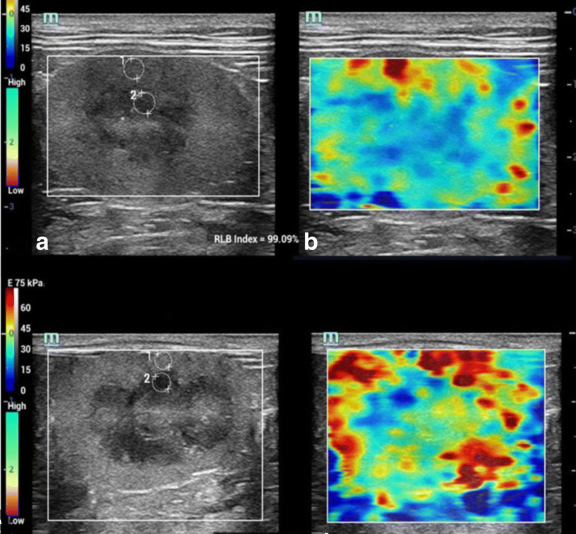

elastography의 신부전 고양이 환자 적용.

몇년전부터 초음파 관련하여 상당히 핫 했던 주제가 elastography 즉, 탄성계측영상이 고양이 신부전에서 사용되면 그 중증도를 확인 할 수 있지 않을까? 였다.

거기에 대한 가능성에 대한 조사 연구도 많았고 실증적으로 효과가 추산된다는 논문도 있었기에 상당히 많은 수의사들이 기대했던 주제다.

그러나 아쉽게도 이번 논문은 이런 기대를 산산히 부셔버렸다.

더 많은 연구가 필요하겠지만 신부전 환자와 정상 고양이간에 탄성도에 크게 차이가 없었다는것.

그리하여 임상적으로 이용하기에는 어려움이 있다는 언급이다.

모든 논문은 현재까지의 주장을 말하는것이란것을 생각해 볼때 차후에는 어떤 조건들을 추가하여 의미 있는 데이터를 끌어낼지는 모르지만 지금으로서는 의미를 두면 안될것으로 생각된다.